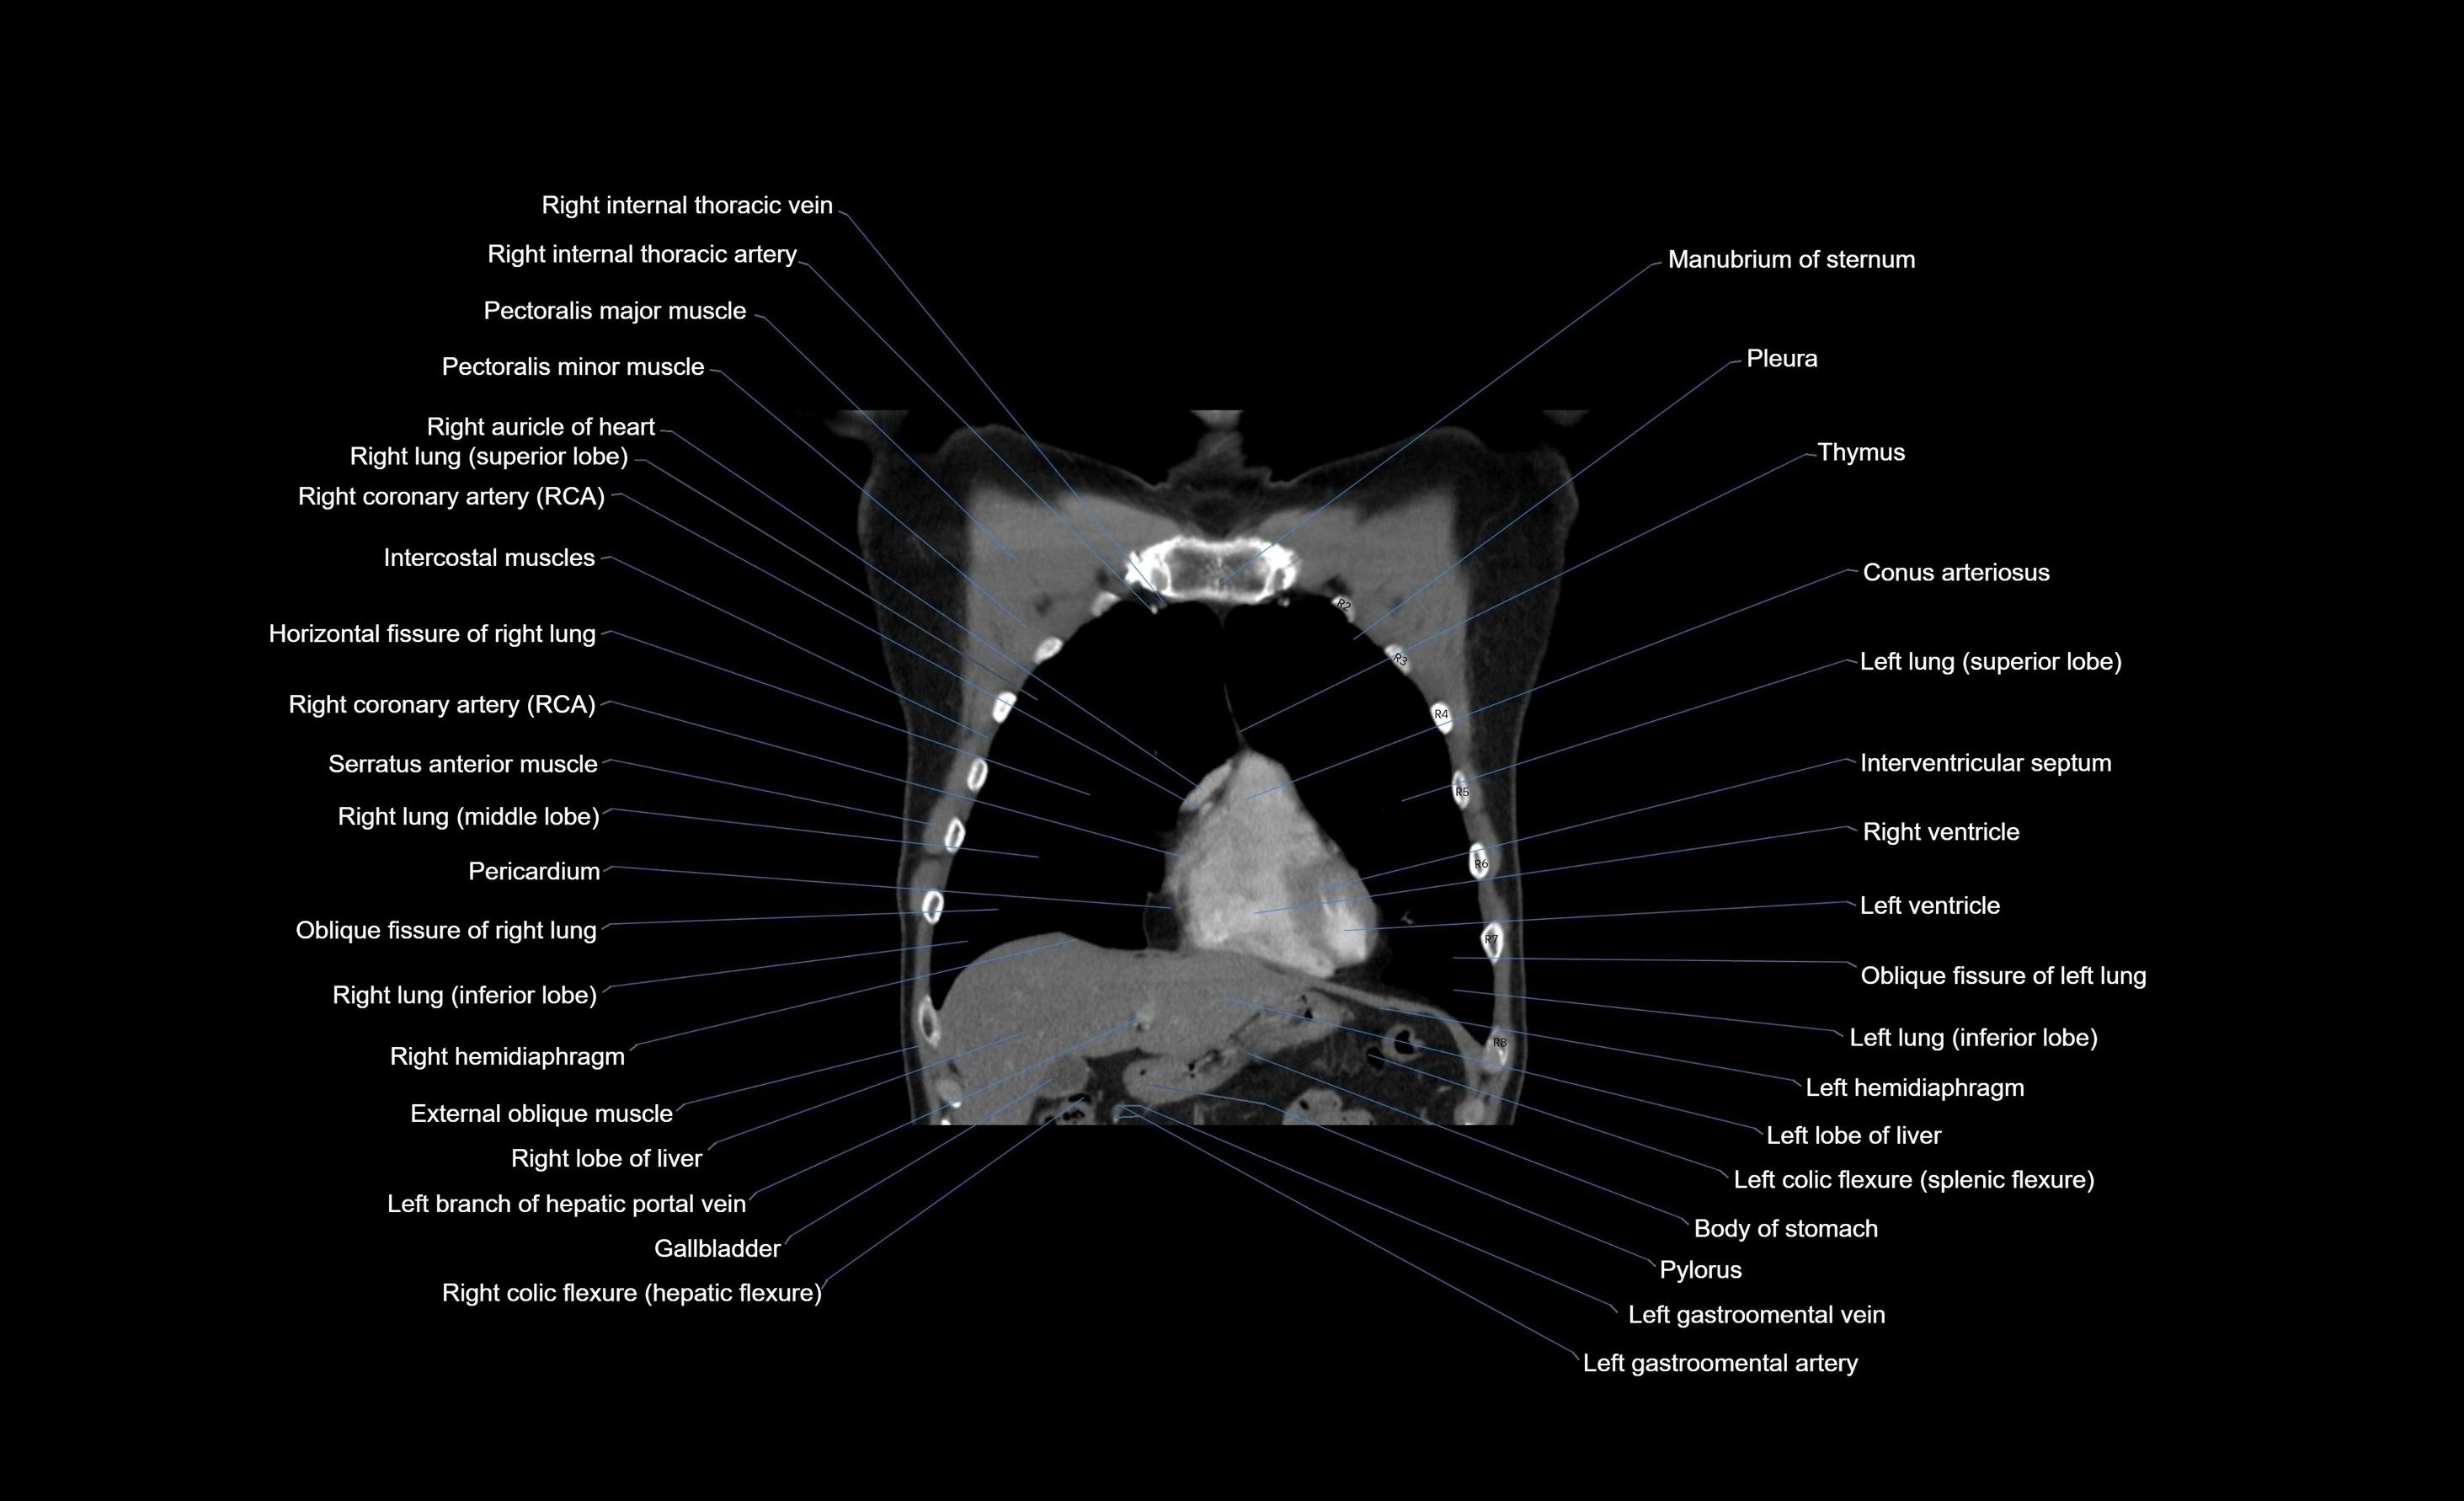

- Right atrium

- Right ventricle

- Left ventricle

- Left atrium

- Middle lobe of right lung

- Right lung (middle lobe)

- Right lung (superior lobe)

- Right lung (inferior lobe)

- Horizontal fissure of right lung

- Oblique fissure of right lung

- Oblique fissure of left lung

- Gallbladder

- Right lobe of liver